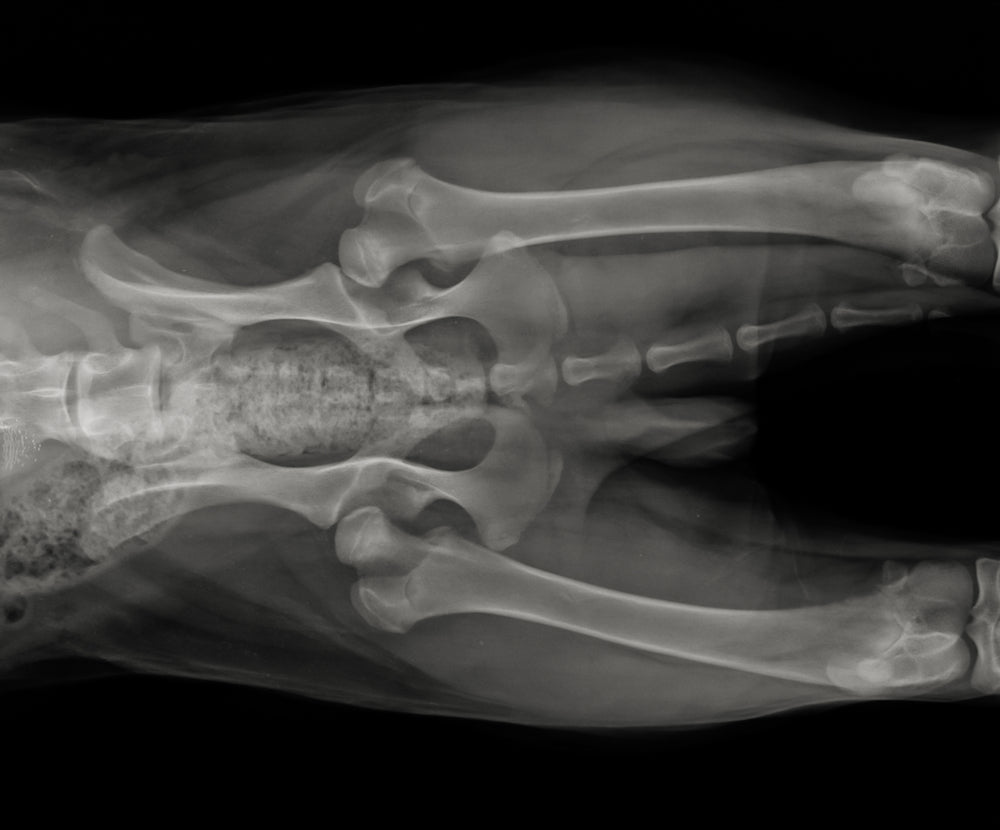

Diagnosis

Diagnosing hip and elbow dysplasia involves a combination of clinical examination and diagnostic imaging. Your vet will assess your dog's gait, range of motion, and joint stability. X-rays are the most common diagnostic tool, but in some cases, advanced imaging such as CT or MRI scans may be recommended.